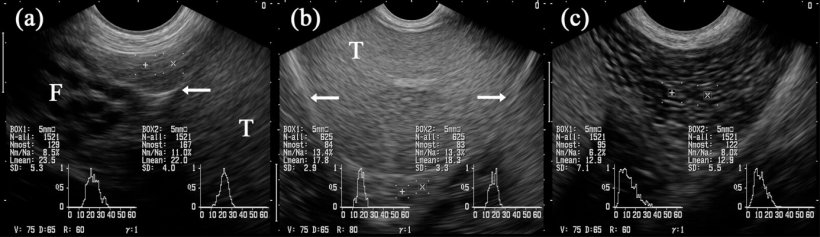

En général, le tissu de l'épididyme est également d'une échostructure homogène et régulière, en étant plus fine dans la tête et le corps et légèrement marbré dans la queue (figure 5A-C). Cependant, l'échogénicité, déterminée par l '« analyse des niveaux de gris », et donnée comme la valeur de gris moyenne, diffère légèrement entre les trois segments, avec des changements dans les images obtenues en comparant avant et après la collecte de la semence (Kauffold et al., 2011) du verrat.

Figure 5: images échographiques des segments épididymaires: caput (= tête, a), corpus (b) et cauda (= queue; c). Les cases marquées « + » et « x » sont projetées sur les segments respectifs de l'épididyme. Testicule (T). Adjacente à la tête il y a plusieurs structures tubulaires identifiées comme étant des parties du funiculus spermaticus (F). Les flèches indiquent la couverture séreuse du testicule (c'est à dire la bursa) testicularis. (Kauffold et al., 2011)